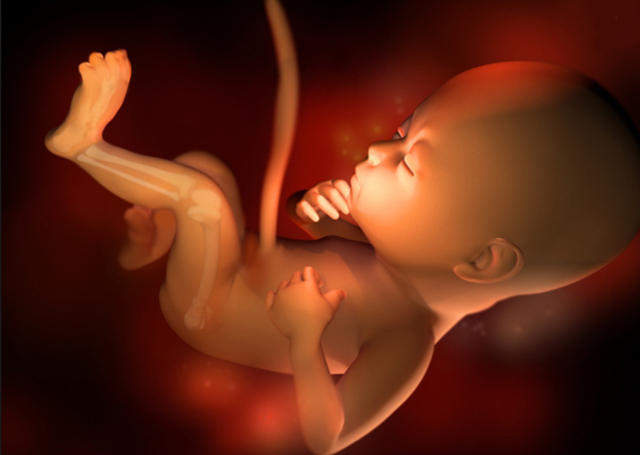

• Semana 40

Semana 40

-Los órganos están maduros.

-El peso promedio es de 3.250g o más

-El feto esta listo para nacer